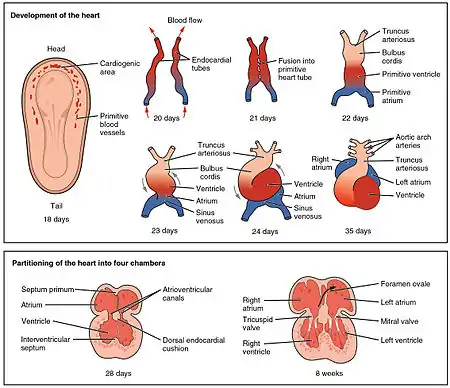

Development

The muscular part of the interventricular septum derives from the bulboventricular flange which is developed due to differential growth of primitive ventricle and bulbous cordis. Membranous part has a neural crest origin which connects the upper free margin of the bulboventricular flange and anterior and posterior endocardial cushions of atrio ventricular canal. It also gets attached to lower border of spiral septum or the aorticopulmonary septum.

In the final stages of the heart development, the interatrial septum aligns in the same plane as the interventricular septum. The gap between the interatrial septum and interventricular septum forms the membranous part of interventricular septum. [3]